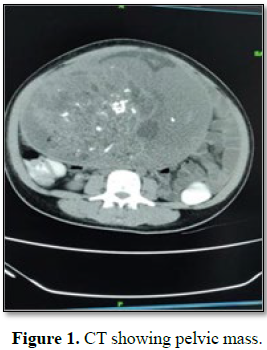

ovary. There was no evidence of free fluid in the abdomen. The contrast

enhanced CT (Figure 1) showed

heterogeneously enhancing multiloculated solid-cystic mass lesion in the left

adnexa (13.7 × 20.9 × 23.5 cm). The cystic area was multiloculated with

enhancing thin septations with multiple central and eccentric calcification and

peripheral enhancing thin margins. Tumor markers levels were elevated (CA-125 –